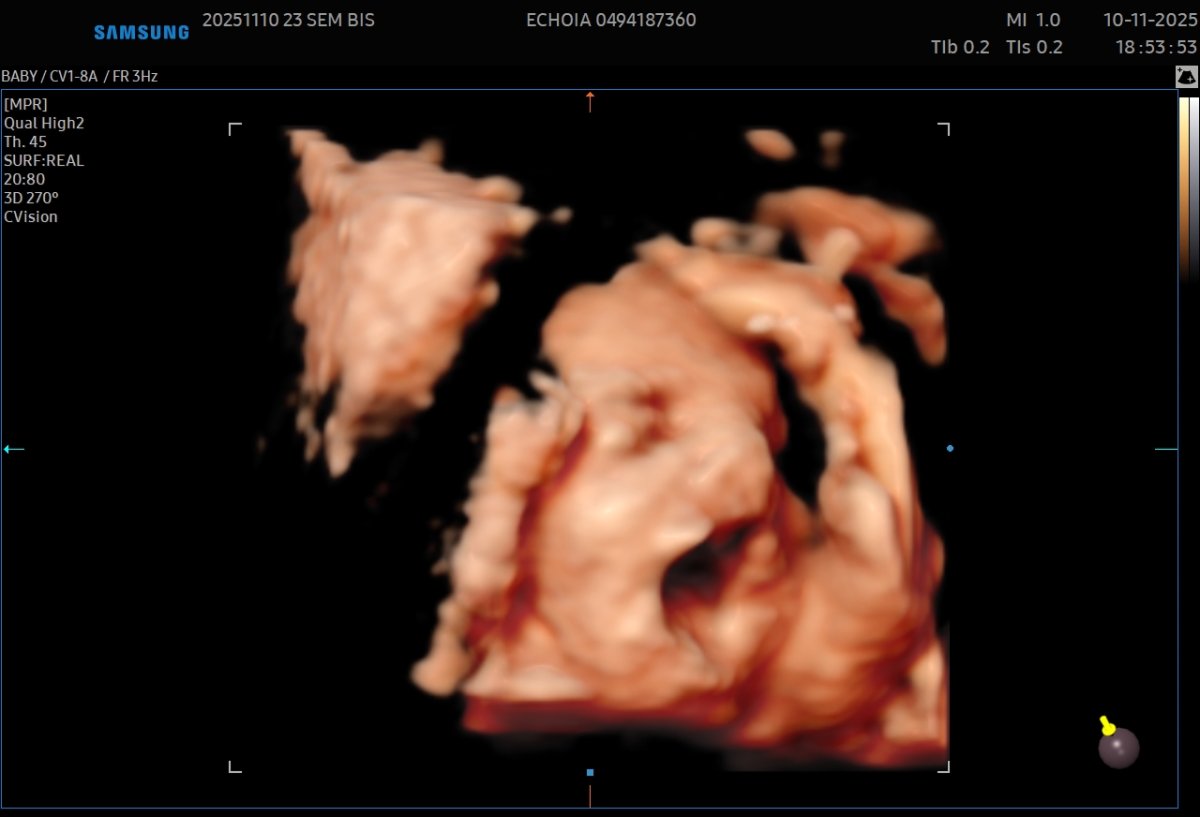

Gallerie de photos